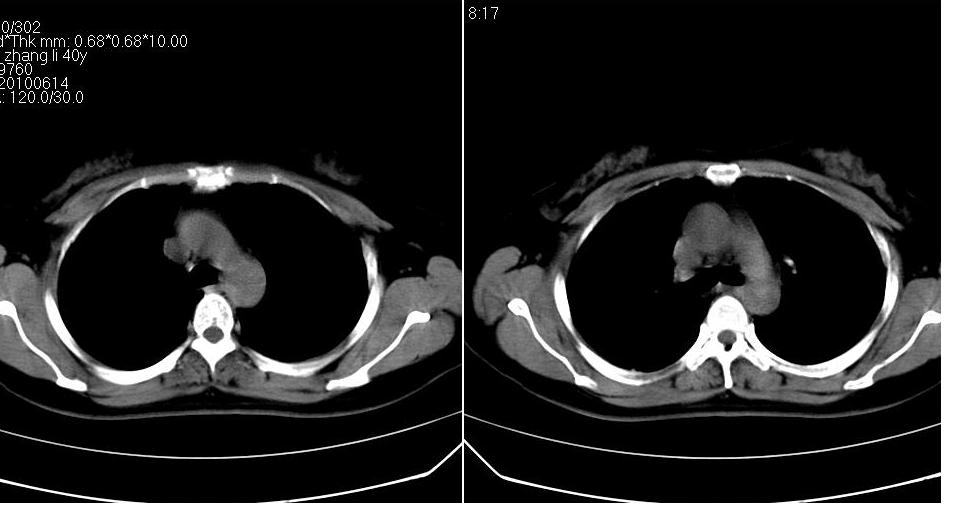

女 40岁,胸片体检发现右肺肿块,无任何症状。

下叶背段多发性小腺泡结节,考虑结核。

考虑侵润性结核

考虑右肺下叶背段继发性肺结核。